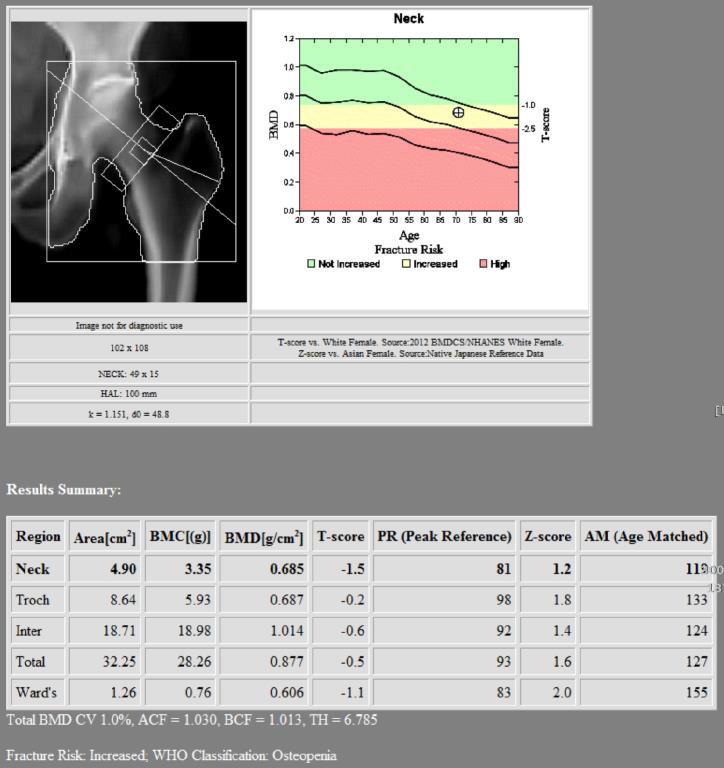

骨質密度攝影檢查可以測量您的骨質密度,將您的骨質密度與已經確立的骨質密度

平均值或標準值進行比較,可以計算出一個比較值;本院新進HOLOGIC的骨質密度測量

儀可測量髖關節、腰椎及全身骨骼密度,可用於骨骼骨質密度評估和骨折風險評估;檢查

骨質密度的量度標準是T評分 (T-score),用來介定是否患上骨質疏鬆症。方法是將雙

能量X光吸收儀得出的T-分,把骨質疏鬆程度分類的骨質密度與處於骨質密度高峰期的同種

族年青人作出比較,以顯示骨質流失的

程度。

以下是根據世界衞生組織的標準,用雙能量X光吸收測量儀得出的T-分把骨質疏鬆程度分類:

世界衛生組織根據骨質密度水平對於骨質疏鬆症的分級方式

骨質密度檢測結果(T評分)

高過-1

-1至-2.5

低於-2.5